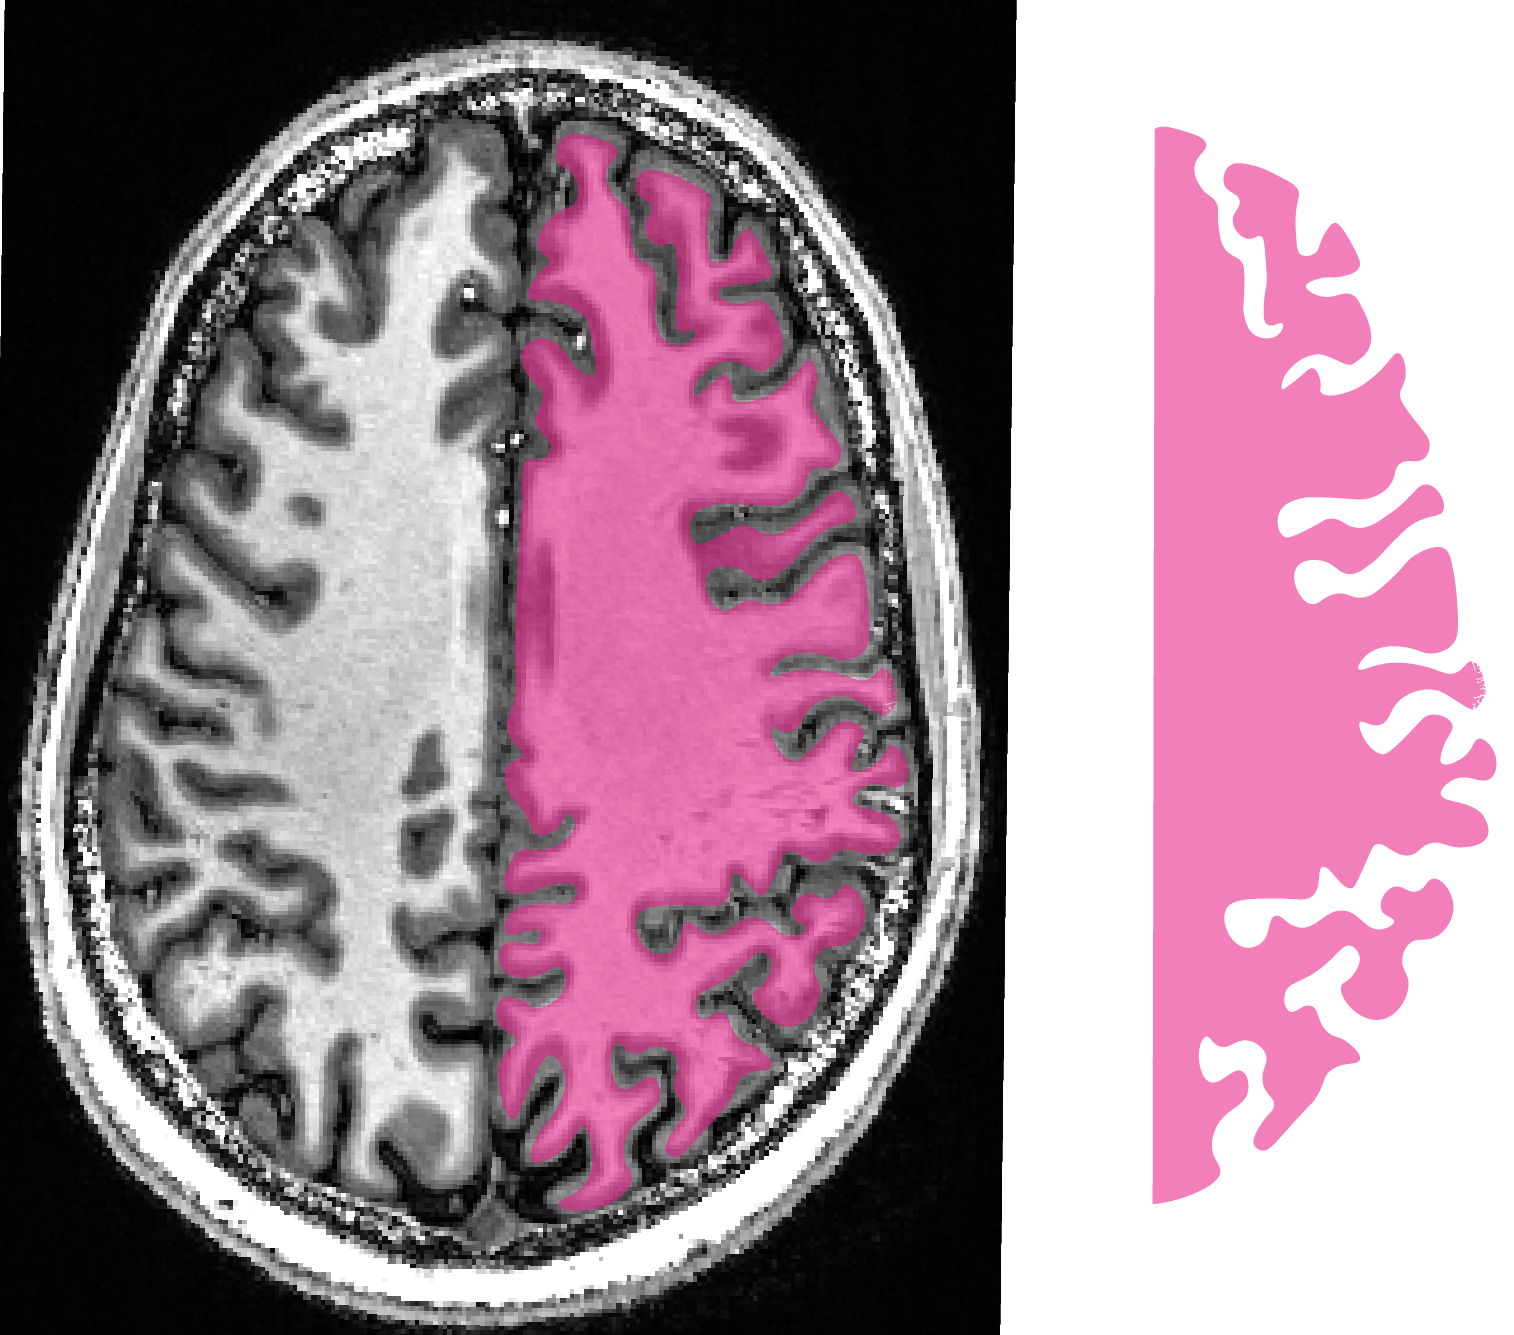

In this this Hackathon project, we aim to develop a purely uni-directional (safe) data streaming “hack” to transfer MRI data directly to the cloud by means dynamic QR codes.

In the early days of the Internet, modems (modulator-demodulator) were used to (i) convert digital information into audio streams, (ii) transfer them across telephone lines, and (iii) convert them back into the digital domain. Here, we aim to do the same thing with pixel data of MRI scans. However, instead of audio signal we will use machine-readable visual information: QR codes.